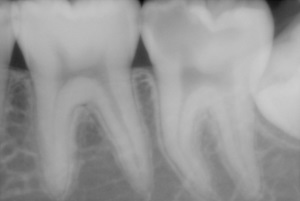

深い虫歯になっておりレントゲンでは神経にまで虫歯が達していると思われました。

神経はすでに腐っているだろうと思い最初はドリルで削り始めると凍みる、痛いという事なので神経がまだ生きている事がわかりました。

そこでライトタッチレーザーとドックベストセメントを用いて患者さんに了承を得た上で神経を残して処置をしていく事にしました。

ライトタッチレーザーで虫歯の部分をある程度取り除いて一層虫歯を残したままでそこをドックベストセメントでふさぎました。